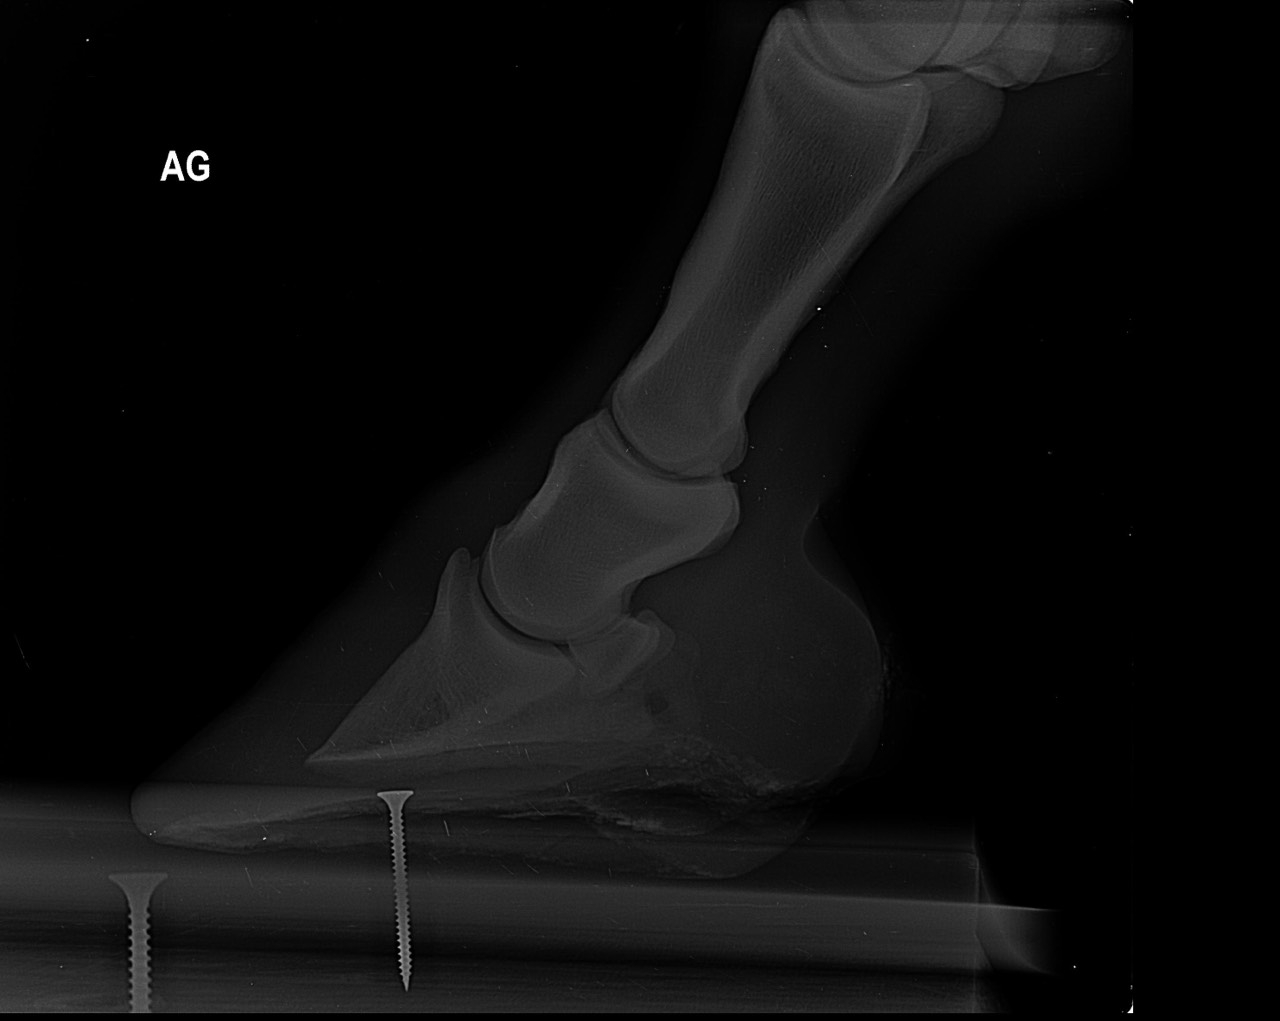

| Dire merci | Je fais un sujet à part pour donner des nouvelles ![]() J’ai fait passer un autre véto pour un 2ème avis. Au début il pensait à un abcès très profond, emplacement détecté avec la pince à sonder. Il a ensuite fait des radios : si j’ai bien compris, la 3ème phalange appuie sur la sole Il y a également de l’arthrose ... Le traitement pour le moment : anti inflammatoires et hipposandales en attendant de pouvoir referrer, et changer de maréchal ferrant. Apparemment il existerait un traitement au laser, le véto va se renseigner. Cody a fait une fourbure l’année dernière, des radios ont été faites à ce moment. J’ai aussi refait des radios de contrôle cette année, il restait une légère bascule de P3. |

| Dire merci | Radios de mai 2023![]() ![]() Radios de juillet 2023 ![]() ![]() Radios d'août 2024 ![]() ![]() |